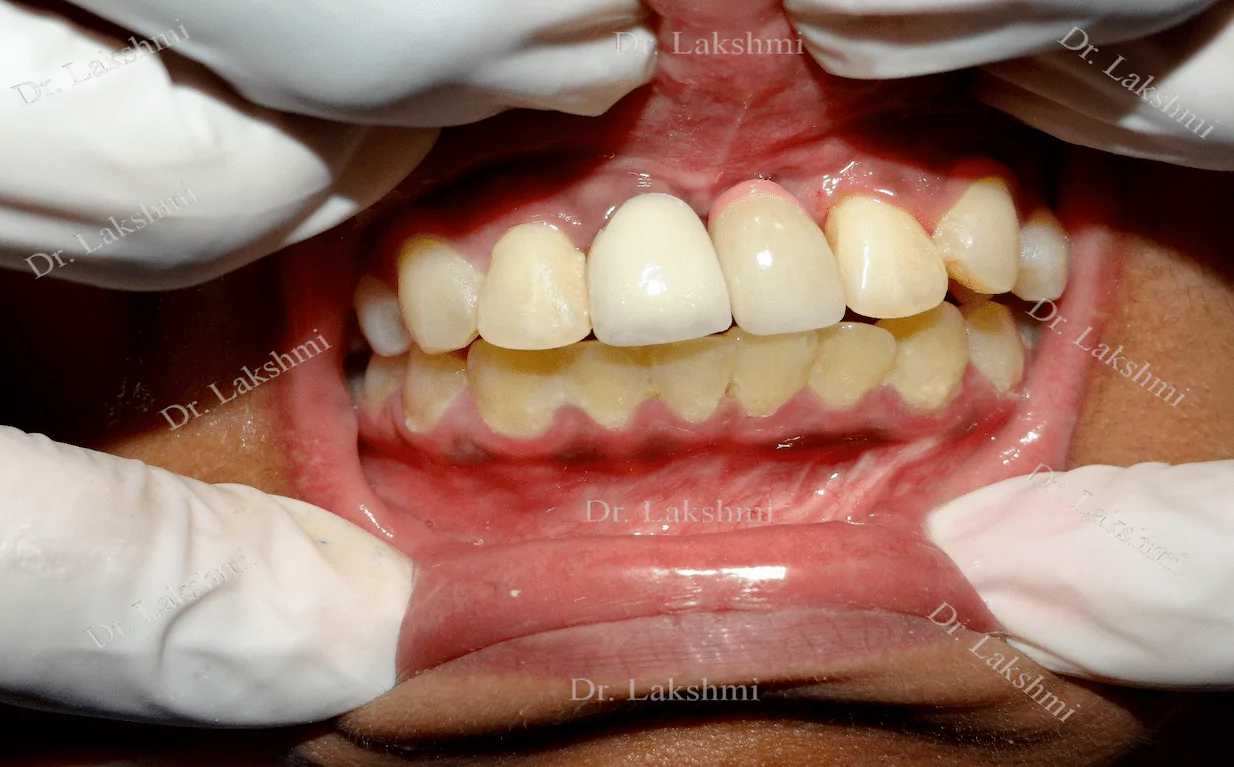

Dental implants have come to define modern dentistry in the last few decades. Dental implants are cemented to the jawbone and an abutment is used as a support for the dental crown that is placed over it. There are a single piece, two-piece and three-piece abutments available for implants. Titanium fuses naturally with the jawbone and that makes it a perfect fit as an implant. There are several dental implant techniques available to opt from, for a patient. The freedom to opt also depends on the condition of the jawbone and the gum.

Requires the placement of a single dental implant (either 2 stage or 1 stage) in the region of the missing tooth, followed by a crown (artificial tooth) over